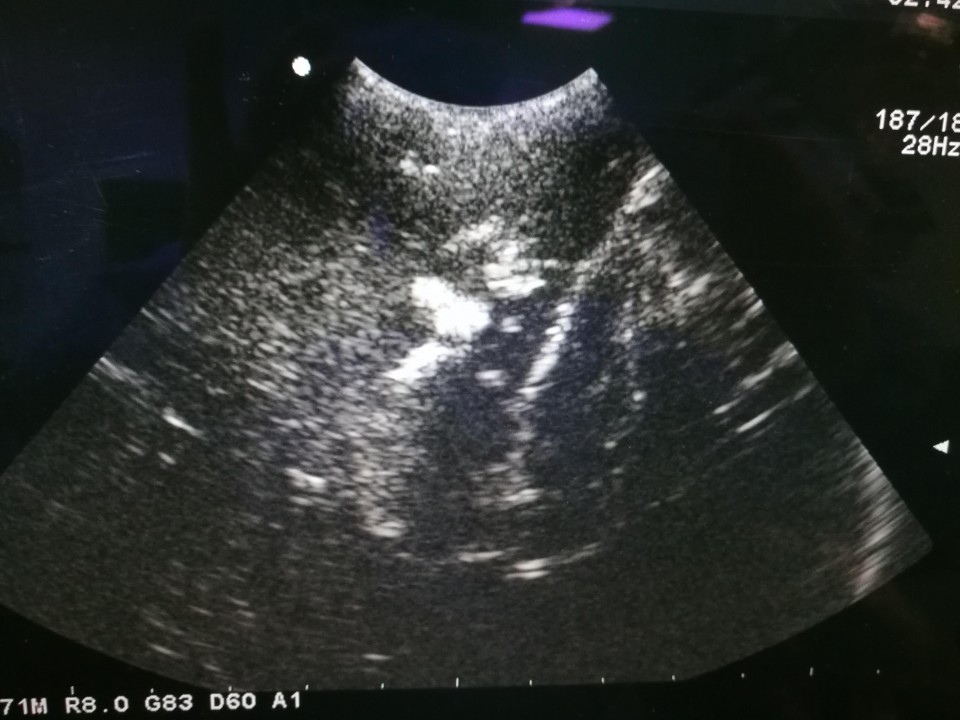

术中B超证实肿瘤全切除

王斌指出,颅内深部多发肿瘤是神经外科治疗难题,因其位置深、病灶多、解剖关系复杂,常规手术造瘘难以完全探及肿瘤且对脑组织损伤大,容易造成患者功能缺失,致使患者难以接受手术。因此,如何更有效的切除脑肿瘤,并且同时尽量减少脑组织损伤,保留患者功能就成为了神经外科研究的热点与焦点。我院神经外科一病区王斌主任团队在开颅显微切除肿瘤的基础上进一步改良创新开展了术中B超引导下一次性切除颅内多发肿瘤术,成功的为这名患者实施了脑肿瘤完全切除,术后患者功能完全正常。(王斌 洪文明)